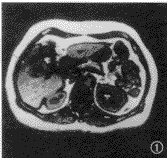

图1,2 患者 男,50岁。肝右叶大片脂肪浸润,不伴有占位病变。反相位序列(TR 128 ms,TE 2.7 ms,翻转角70°)示肝右叶下段低信号片状脂肪浸润(图1),而在同相位(TR 128 ms,TE 5.3 ms,翻转角70°)上呈等信号,无法区别(图2)